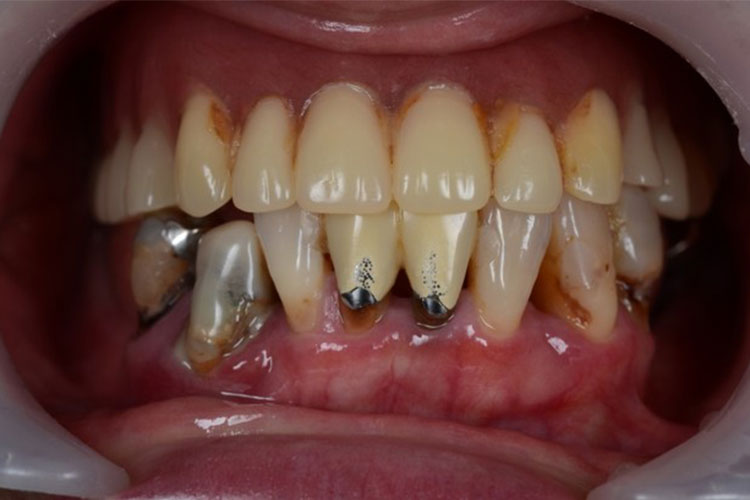

All-on-4症例 Case2

Treatment cases

Before

After